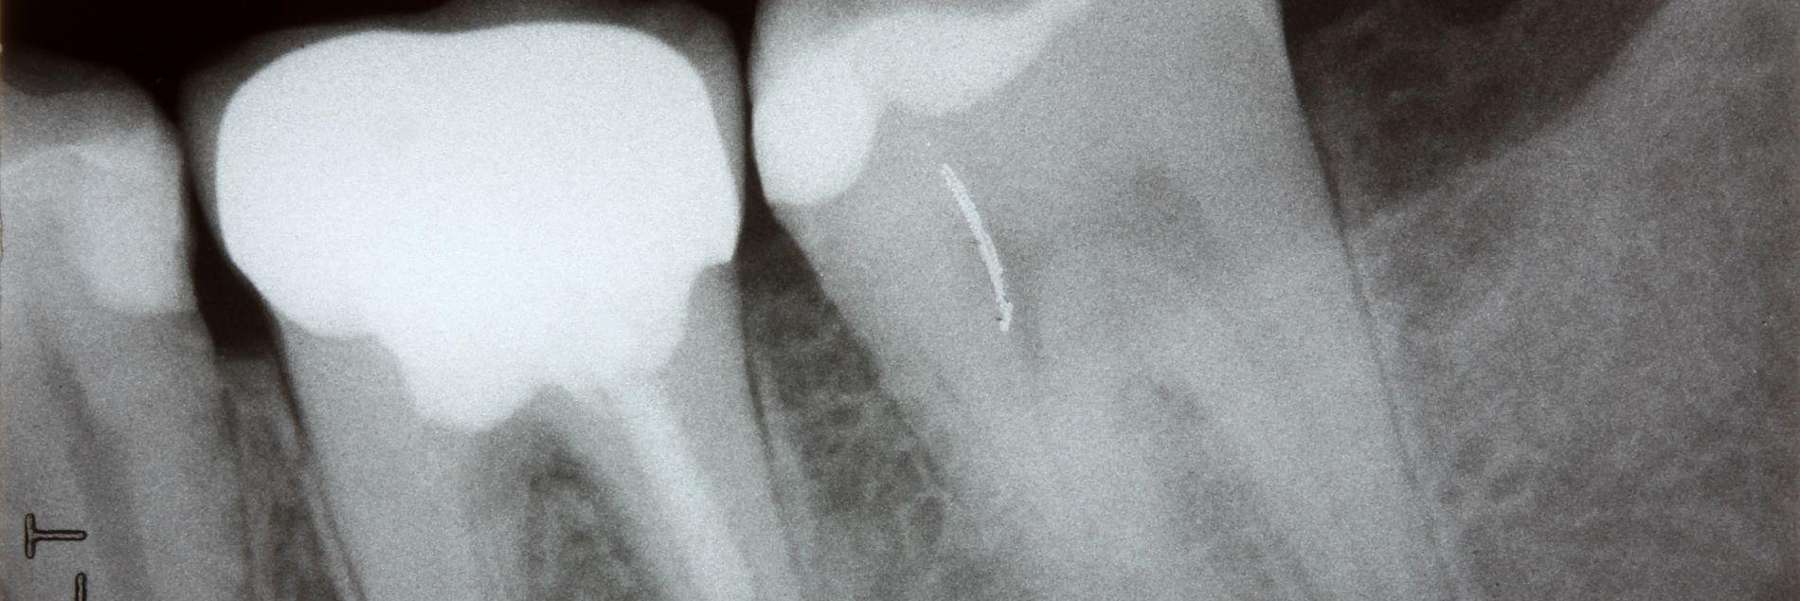

image of wisdom teeth in doreen vic

Sometimes called the “third molars,” wisdom teeth often come in with no issues, but for some, these teeth either come in at an angle or get stuck in your jawbone or gums. This can cause certain oral health issues, including the following:

However, sometimes, your wisdom teeth may be impacted. This means they are coming in at an angle and can’t erupt properly, or there isn’t enough room for them to erupt. When this happens, your dentist may need to make an incision in your gums to access your wisdom teeth and remove them.